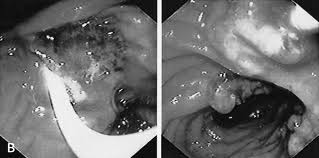

Bệnh nhân tự phát không có triệu chứng có cơn khỏi bệnh không đau sau điều trị không thành công với dẫn chất benzimidazole loại triclabendazole (TCBZ) 3 lần riêng biệt trong suốt hai năm. Anh ta lần đầu tiên điều trị với liều đơn 10 mg/kg TCBZ (Fasinex suspension; Novartis Animal Health Ltd., Surrey, UK), rồi tiếp đến 2 liều cách nhau 24 giờ và lần cuối cùng với 2 liều TCBZ (Egaten; Sipharm Sisseln AG, Sisseln, Switzerland) liều 10 mg/kg mỗi 12 giờ; lần thứ 4 điều trị dùng thuốc với thức ăn. Các mẫu phân vẫn còn dương tính trứng F. hepatica sau điều trị. Hiệu giá kháng thể IgG vẫn dương tính (320, EIA) và sán có thể nhìn thấy qua siêu âm túi mật và ống mật chủ. Ngay sau đó, bệnh nhân được điều trị bằng Nitazoxanide (500 mg x 2 lần/ ngày x 7 ngày); Tuy nhiên, các mẫu phân vẫn còn phát hiện trứng F. hepatica.

A) Siêu âm gan của bệnh nhân nhiễm F. hepatica. B) Vẽ hình của A, mô tả gan màu trắng, ống mật chủ màu xám và tinh mạch cửa màu đen. Một con sán (màu trắng) kích thước dài 2.5–3 cm được xác định trong ống mật chủ. |